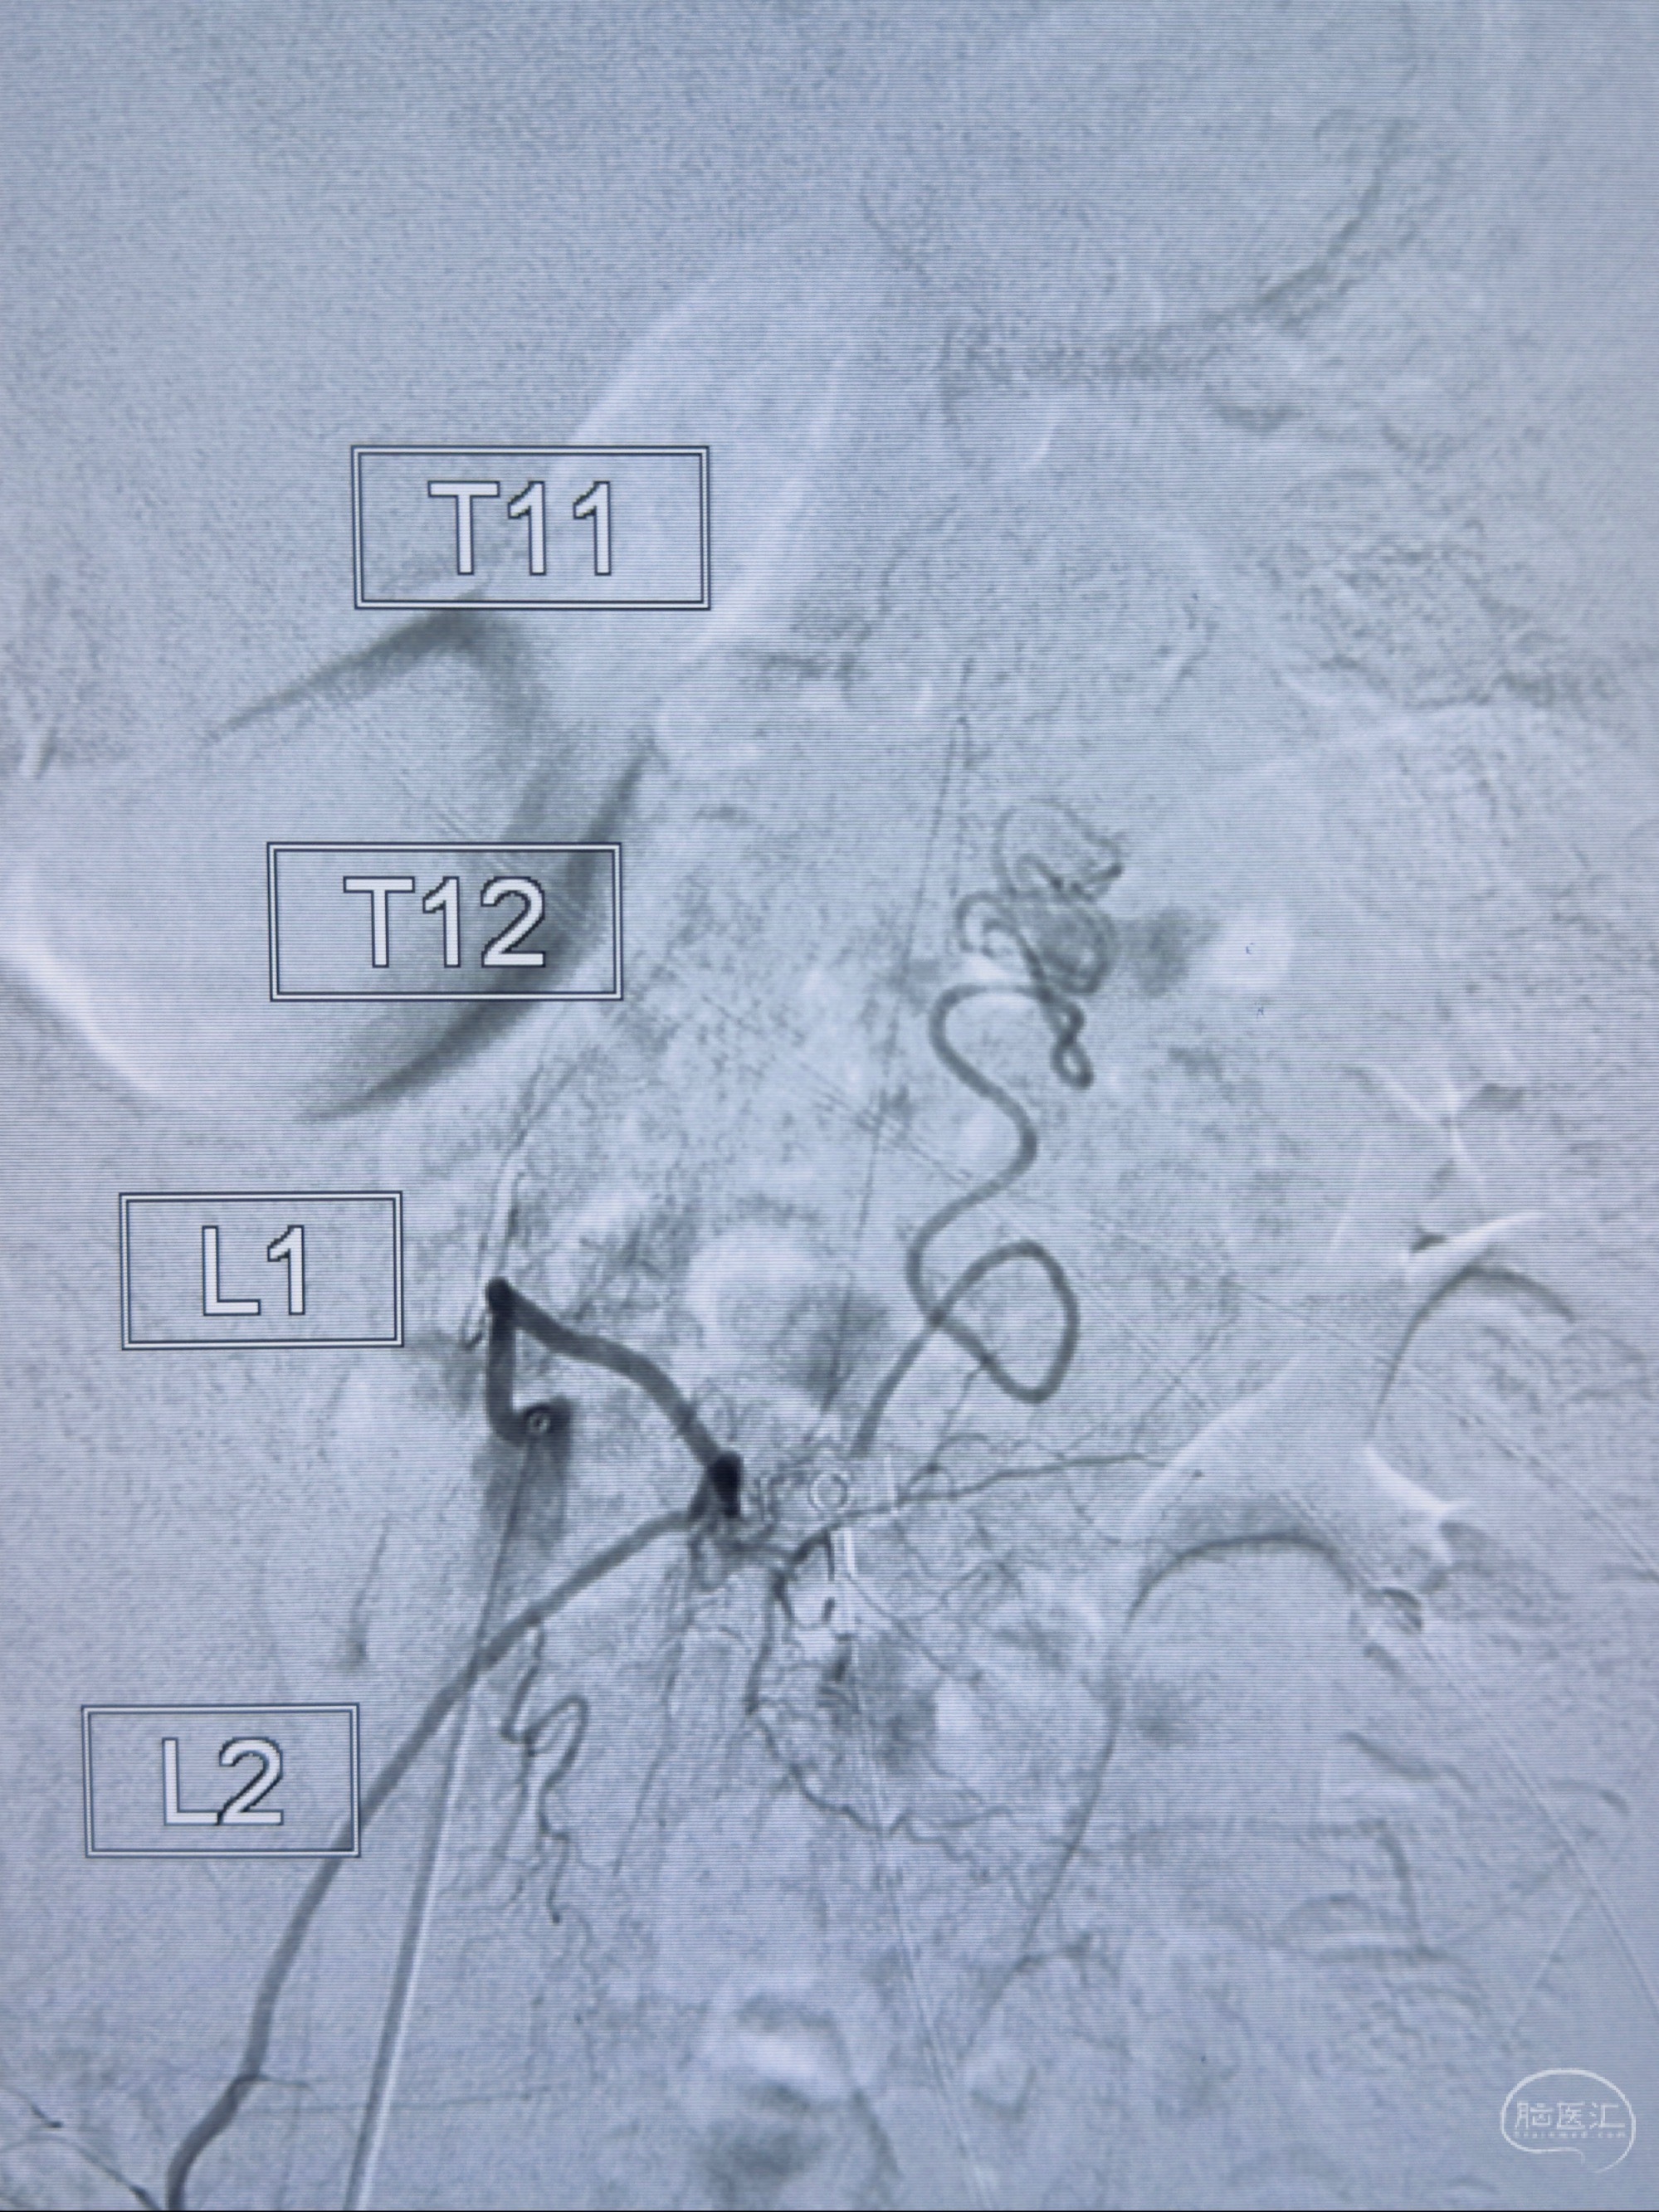

2023-10-13DSA:右侧L1水平硬脊膜动静脉瘘,供血动脉为右侧L1,附近动脉未见明确吻合供血,供血动脉处可见脊髓前动脉发出